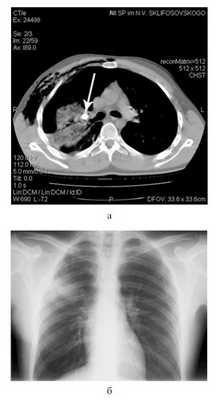

В связи с большим поступлением воздуха по дренажу сразу после этой операции пострадавшему выполнена КТ груди (рис. 6, а): Рисунок 6. Данные обследования пострадавшего Ш. а - компьютерная томограмма перед операцией; б - обзорная рентгенограмма груди перед выпиской из стационара. имелось инородное тело (пуля) в прикорневых отделах правого легкого, сдавливающее просвет верхнедолевого бронха. Травматическая инфильтрация II, III, VI, VII, VIII, IX, X сегментов правого легкого на фоне частичного коллабирования. Несмотря на наличие плеврального дренажа (по Бюлау), на фоне незначительного гемоторакса (230 см 3 ) имелся пневмоторакс большого объема (1100 см 3 ). Определялись эмфизема мягких тканей правой поверхности грудной стенки, перелом II и III ребер справа.

При наличии ран живота выполняли их первичную хирургическую обработку с извлечением пули (рис. 7) Рисунок 7. Интраоперационная фотография: пуля калибра 9 мм в мягких тканях брюшной стенки. и в случае обнаружения проникающего характера повреждения производили срединную лапаротомию (3 наблюдения). При этом в одном наблюдении была повреждена серозная оболочка тонкой кишки, в другом имелся ушиб тонкой кишки (произведена резекция тонкой кишки и наложен энтероэнтероанастомоз) и в третьем - сквозное ранение левой доли печени, сопровождавшееся кровопотерей около 1600 мл.